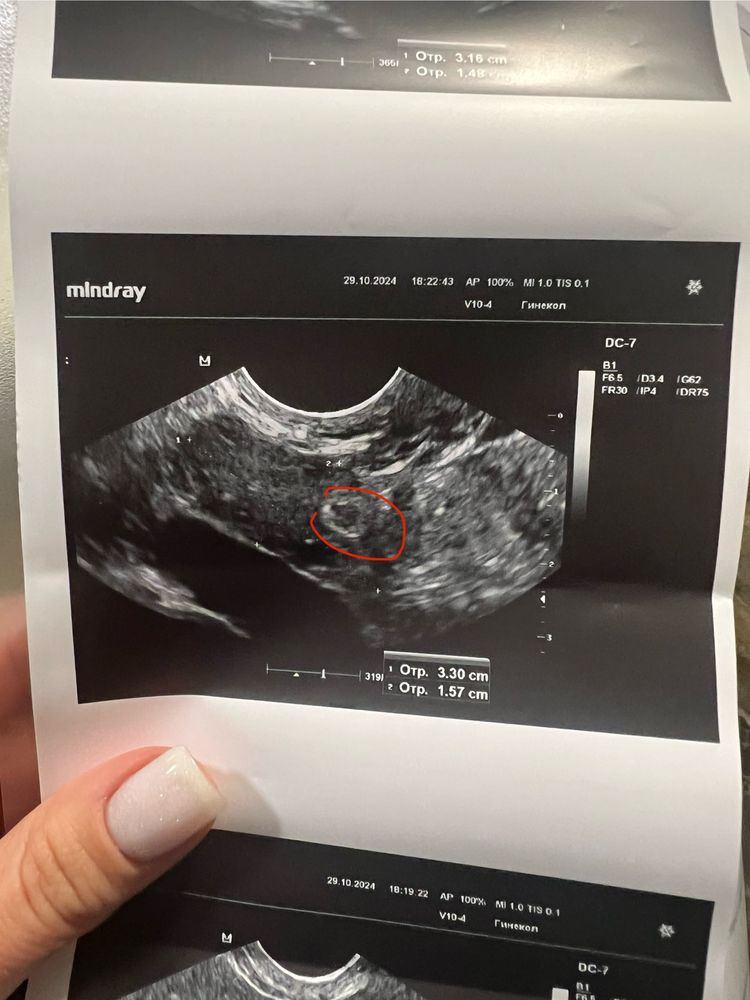

Образование в яичнике по ЗБ

В июле был МА и вакуумная аспирация, вот уже прошли 5-е месячные, пришла провериться на узи, а там меня огорошили каким то функциональным включением в яичнике. Со слов врача, она сказала многие узисты бы такое и не описывали, но Вам вот покажу, выводит монитор и показывает какое-то включение с белым ободком. Сказала оно полностью аваскулярное, спросила это страшно? Вроде бы как нет, такое ощущение, что это не регрессирующее ЖТ, похоже. В беременность овуляция была с права, соотвественно там и было ЖТ, вот не пойму оно с беременности не уходит или что, начиталась в интернете уже про дермоидные кисты и все самое плохое напридумывала, может кто разбирается?

Функциональная киста это или доминантный фолликул который не лопнул или желтое тело, которое не сдулось после овуляции. Пройдёт само через 1-3 цикла. Это не сирашно